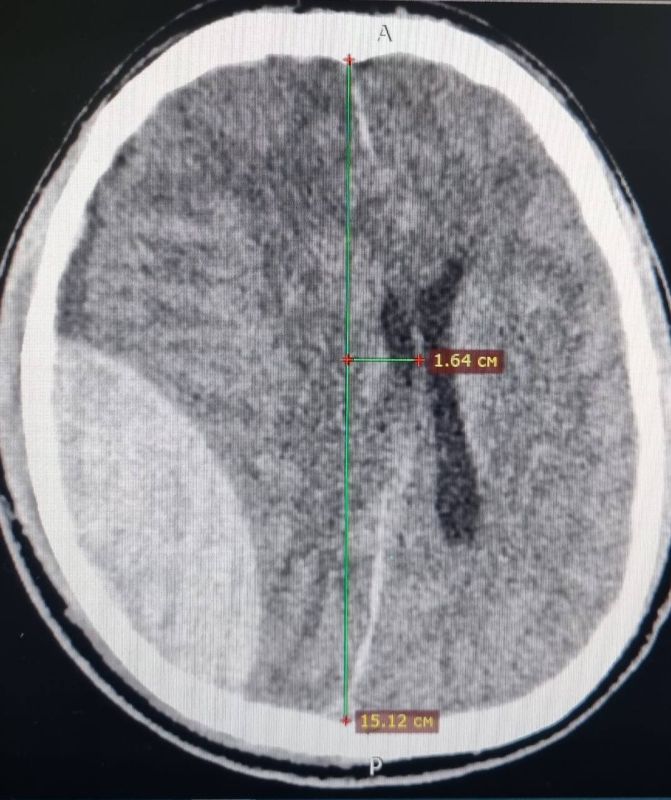

Больше фото в MAX.Жуткой, но удивительной историей поделились в Ессентукской ГКБ. Вечером горожанин оступился, упал с высоты собственного роста и ударился затылком. Он не придал этому значения и лёг спать. Утром близкие не могли его...